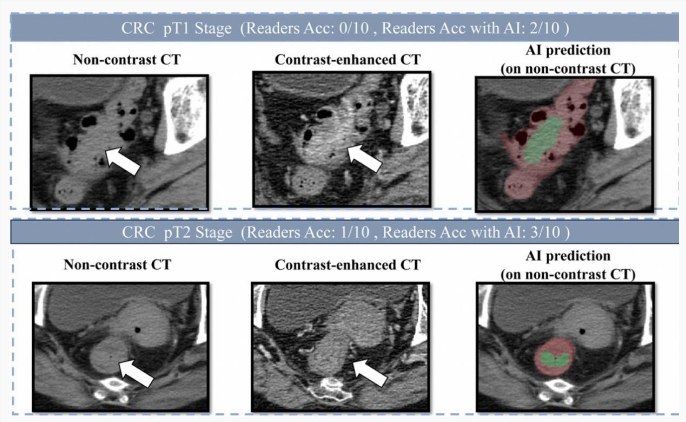

阿里巴巴发布创新癌症AI模型 助力肠癌筛查

阿里巴巴达摩院在医疗领域再度发力,近期联合广东省人民医院等机构,成功研发出一种新的肠癌筛查 AI 模型 ——DAMO COCA。这一模型在 2.7 万份平扫 CT 影像中表现出色,精准识别出 5 例漏诊的肠癌,敏感性和特异性分别达到 86.6% 和 99.8%。这意味着,借助这一技术,医生在筛查肠癌时的误诊率将大幅降低。

肠癌,作为结肠癌和直肠癌的统称,在全球范围内是导致癌症死亡的第二大原因。尤其在 30 岁以下的人群中,发病率呈现上升趋势。专家们指出,早期发现肠癌对提高患者的生存率至关重要,早期发现的患者五年生存率可达到 90% 以上,而晚期患者的生存率则仅为 14%。然而,传统的肠癌筛查方法如粪便隐血检查和肠镜检查常常让人感到不适,导致很多人对筛查心存顾虑。

达摩院的创新性方案通过 “平扫 CT+AI” 实现了无创筛查。平扫 CT 在国内广泛用于健康体检和创伤评估,每年生成的影像数量惊人。借助 DAMO COCA 模型,医生可以利用这些常规检查的数据进行肠癌筛查,而无需患者进行额外的准备工作。这一方法将显著提高筛查的接受度,帮助更多人及时发现肠癌风险。

为克服肠道内容物对影像的干扰,达摩院的技术团队采用了 “先定位、后诊断” 的深度学习架构,并专门针对小于 3 厘米的早期肿瘤进行训练。这种两阶段的学习策略,使得 AI 模型能够有效地分割复杂的肠道区域,从而更准确地检测出可疑病灶。

自 2017 年成立以来,达摩院在医疗 AI 领域不断探索,之前已研发出胰腺癌筛查 AI 模型 DAMO PANDA 和胃癌筛查 AI 模型 DAMO GRAPE。随着 DAMO COCA 的推出,达摩院的 “平扫 CT+AI” 多癌筛查技术路线已正式运行,并在多个癌症筛查方面取得了显著进展。